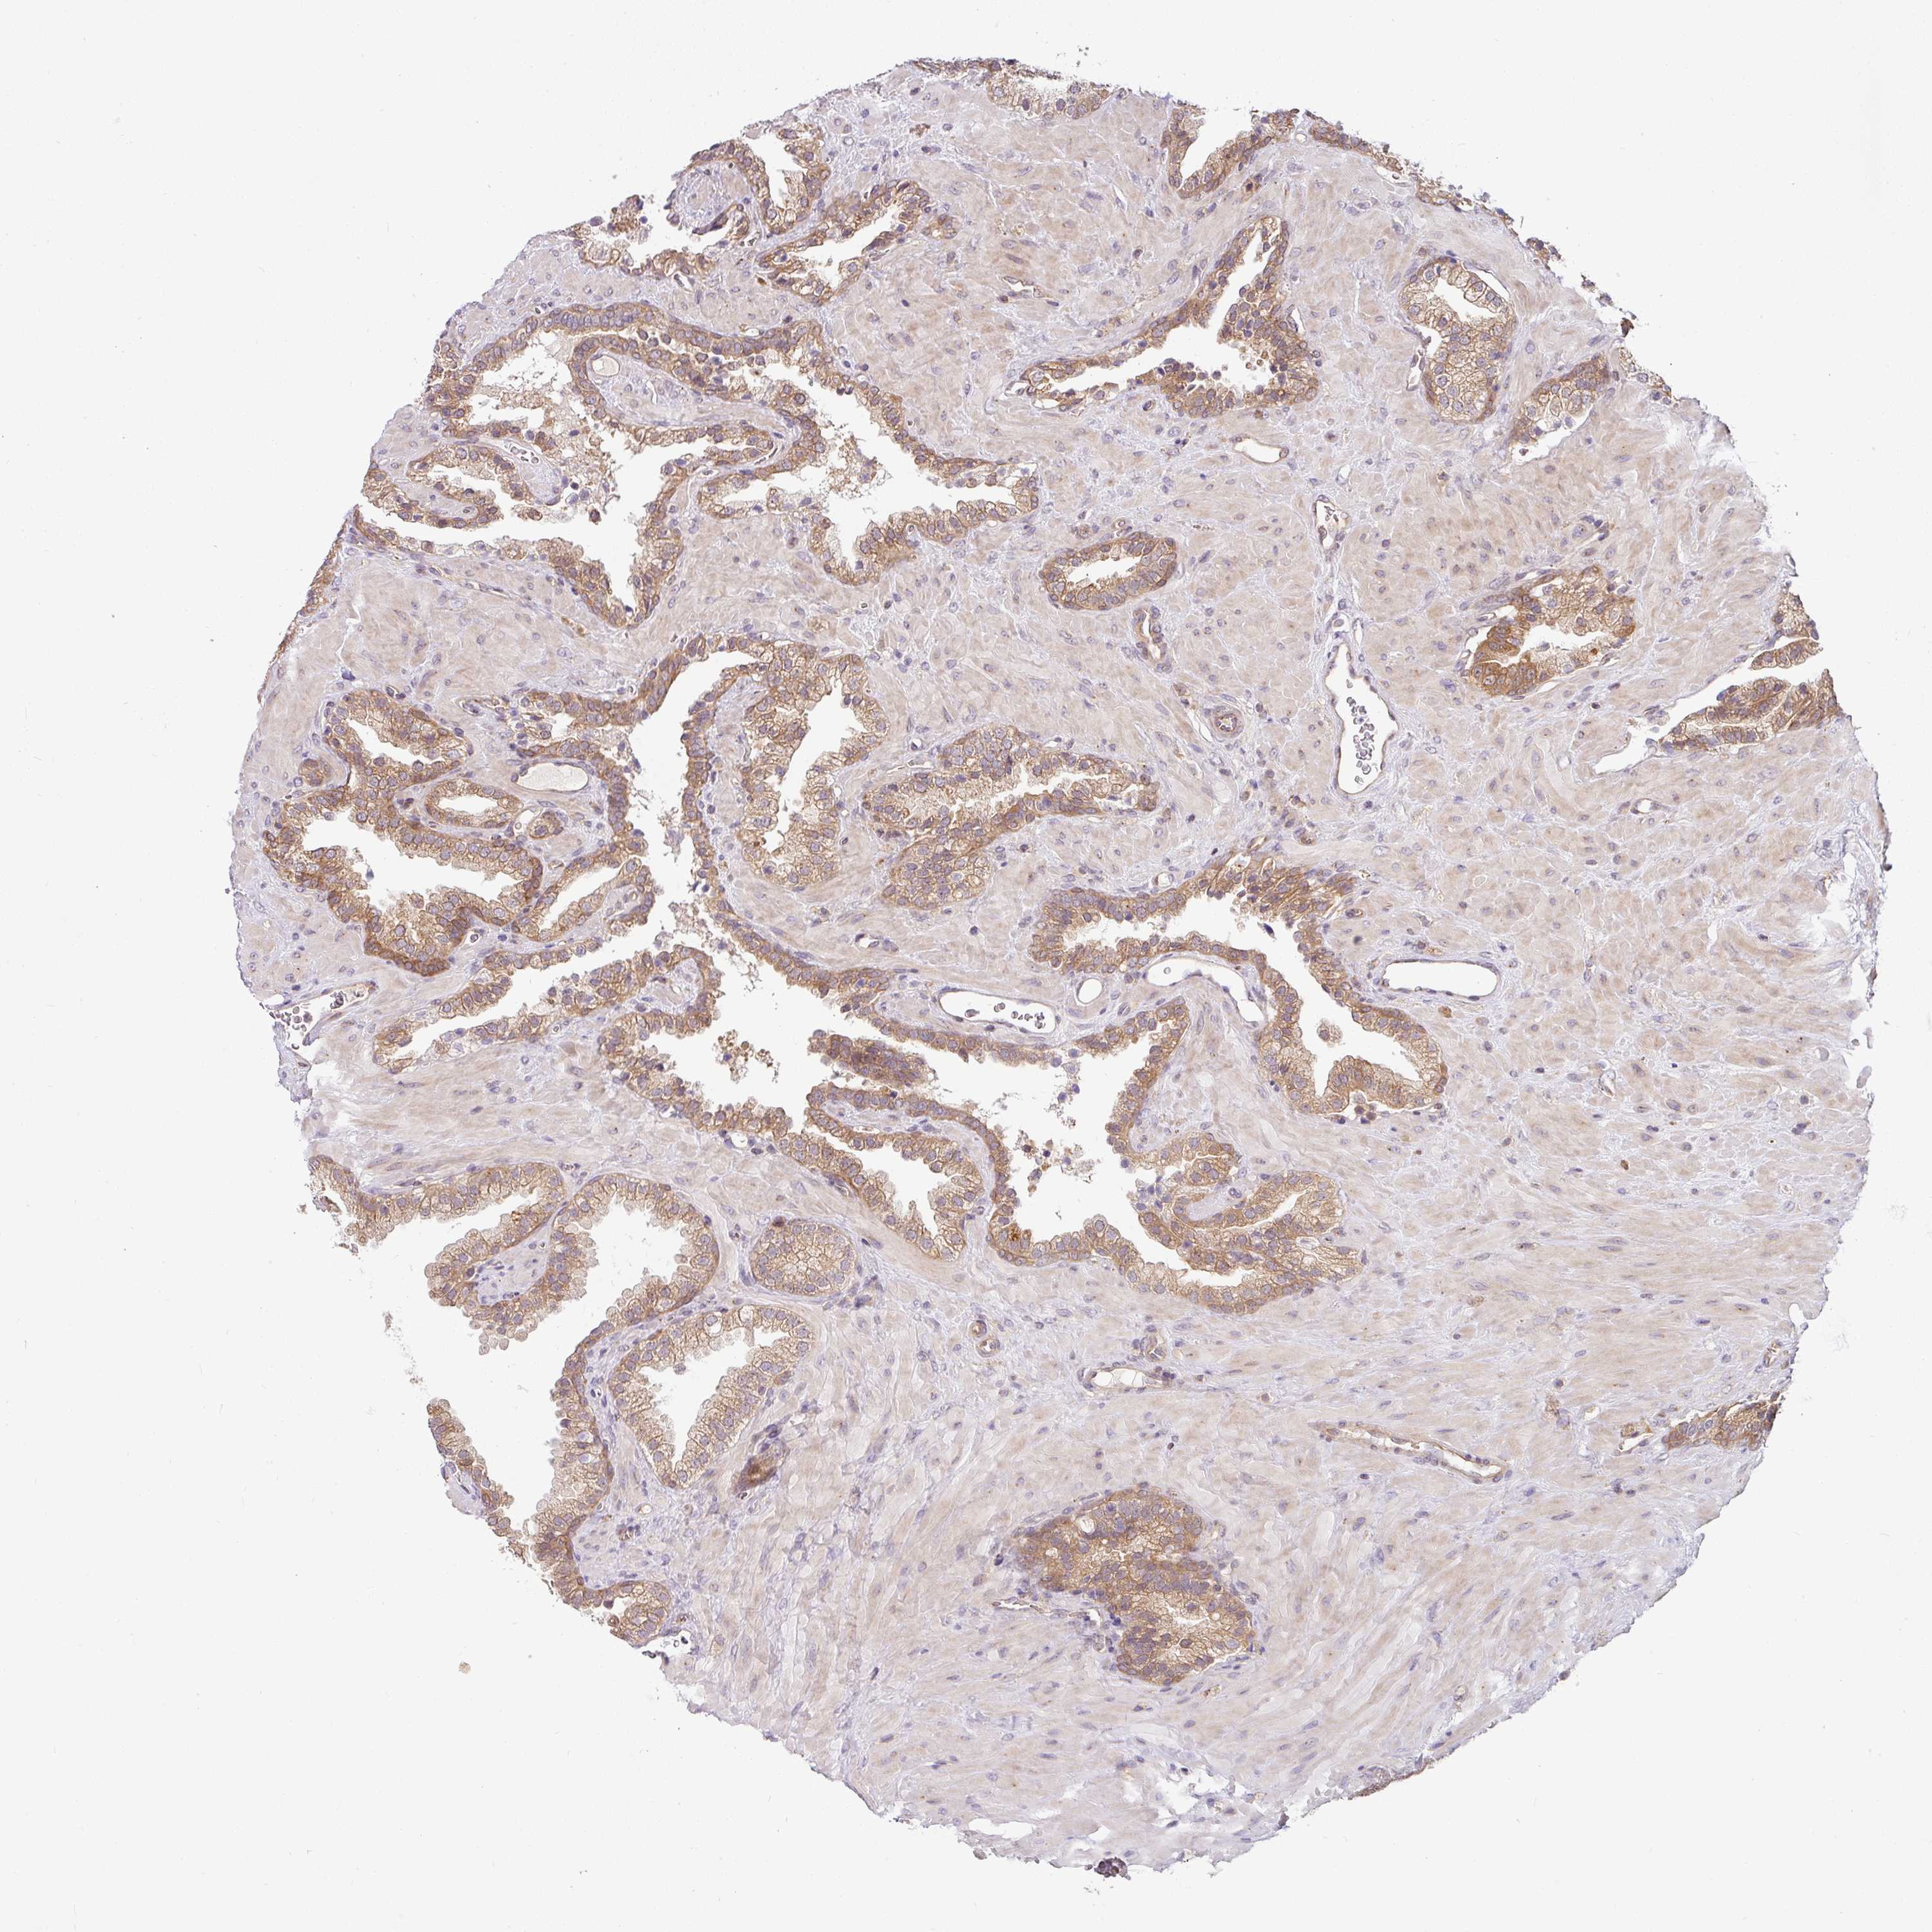

PROSTATE CANCER - Protein expressioni

A mouse-over function shows sample information and annotation data. Click on an image to view it in a full screen mode. Samples can be filtered based on level of antibody staining by selecting one or several of the following categories: high, medium, low and not detected. The assay and annotation is described here.

Antibody stainingi

Antibody staining in the annotated cell types in the current human tissue is reported as not detected, low, medium, or high, based on conventional immunohistochemistry profiling in selected tissues. This score is based on the combination of the staining intensity and fraction of stained cells.

Each image is clickable and will lead to virtual microscopy that enables deeper exploration of all samples and also displays staining intensity scores, fraction scores and subcellular localization as well as patient and tissue information for each sample.

Antibody HPA049911

Antibody CAB010161

Staining

High

Medium

Low

Not detected

Intensity

Strong

Moderate

Weak

Negative

Quantity

>75%

75%-25%

<25%

None

Location

Nuclear

Cytoplasmic/membranous

Cytoplasmic/membranous,nuclear

Adenocarcinoma, High grade

Adenocarcinoma, Low grade

Adenocarcinoma, NOS